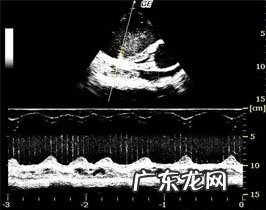

超声心动查验

超声心动查验:全部心腔均比较严重扩大 , 收缩期左心房內径LVDS 57.毫米(14.9~25.毫米) , 显著扩大 , 及其减少成绩FS=25%(33~46%)和射血分数EF减少 , EPSS扩大 , 提醒心房收拢作用较弱 。室中隔和左心房分散壁薄厚减少 。左心房LA/AO=3.64 , 提醒左心比较严重扩大 , 心力衰竭产生 。多谱勒精确测量二尖瓣返流 , 则继发性于心房比较严重扩大后 。